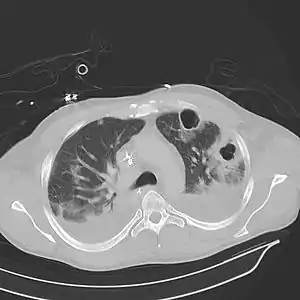

![]() Картина абсцесу легені при комп'ютерній томографії. Видно порожнину у тканині легені. Картина абсцесу легені при комп'ютерній томографії. Видно порожнину у тканині легені. | |